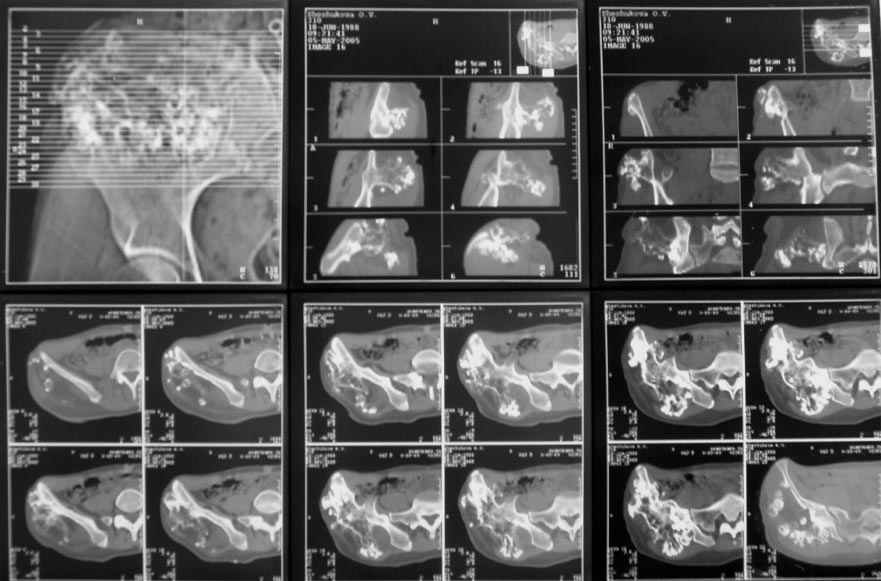

Судя по КТ, проблема не в гребне а в крыле...

Опухоль имеет задне-наружное нправление...

В таких ситуация 3D реконструкция по КТ - идеальная вещь...

По-моему, КТ-картина наводит на мысль об озлокачествлении (резкая неоднородность, местами размытие контуров) - вторичной хондросаркоме. Местами, кстати, имеется рост и в направлении брюшной полости. Для решения вопроса об объеме резекции в данном случае оправдана трепанобиопсия. Если это хондросаркома, особенно низкодифференцированная, то стоит обсудить возможность удаления всего крыла с окружающими мягкими тканями. Вариант реконструкции - комбинированная пластика аллотрансплантатами. А вот какими - зависит от наличия костного банка и возможностью индивидуального изготовления трансплантатов. При отсутствии таковой не лучше ли направить ее в ЦИТО?